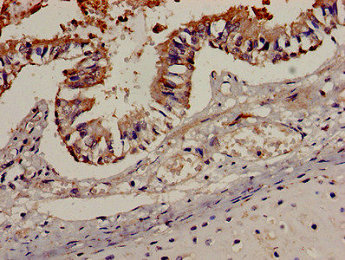

Immunohistochemistry analysis of human lung tissue using CSB-PA004846LA01HU at dilution of 1:100

Immunocytochemistry analysis of human tonsil tissue using CSB-PA004846LA01HU at dilution of 1:100